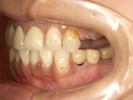

50代女性

歯がこのままではダメだと思い、一念発起された50代女性の方です。

もちろん治療期間が長期にかかることも、治療費が高額になることも、外科的な手術が何度か必要であることなど、

インプラント治療と咬み合わせ治療のほぼ全てを大名歯科ホームページで予め知っていただいた上で決心され来院されたそうです。

インプラント治療は顎骨が乏しかったため、増骨手術も併用しなければならない難症例でした。

治療期間中は残存歯数が少ない上に、丈夫でないため生活に不自由な点がでました。

さらに咬み合わせが安定しにくい症例のため、プラスチック仮歯がよく壊れたり、外れたりして、修理に来院していただくなど大変な苦労とご迷惑をおかけしました。

審美性(見た目)は十分回復できたと思っており、患者さんも大変満足されています。

食事は当然のことかもしれませんが、よく咬めるようになったそうです。

咬み合わせ治療は非常に難しいため、これで十分かどうか分かりませんが現在もこのまま定期的なメインテナンス中です。